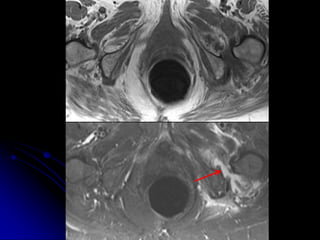

INCIDENTAL

FINDINGS &

COMORBIDITIES